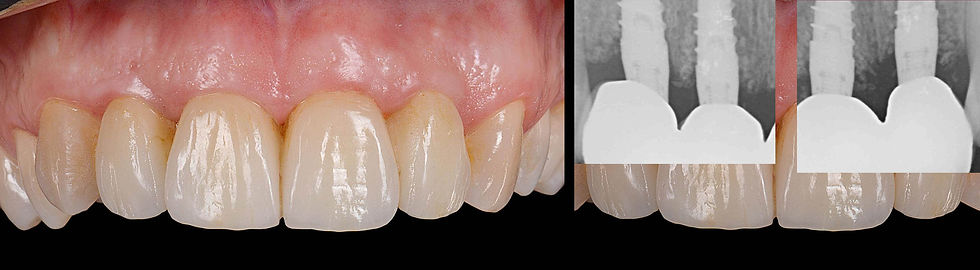

Clinical aspect and radiographic images overlap after 12 months.